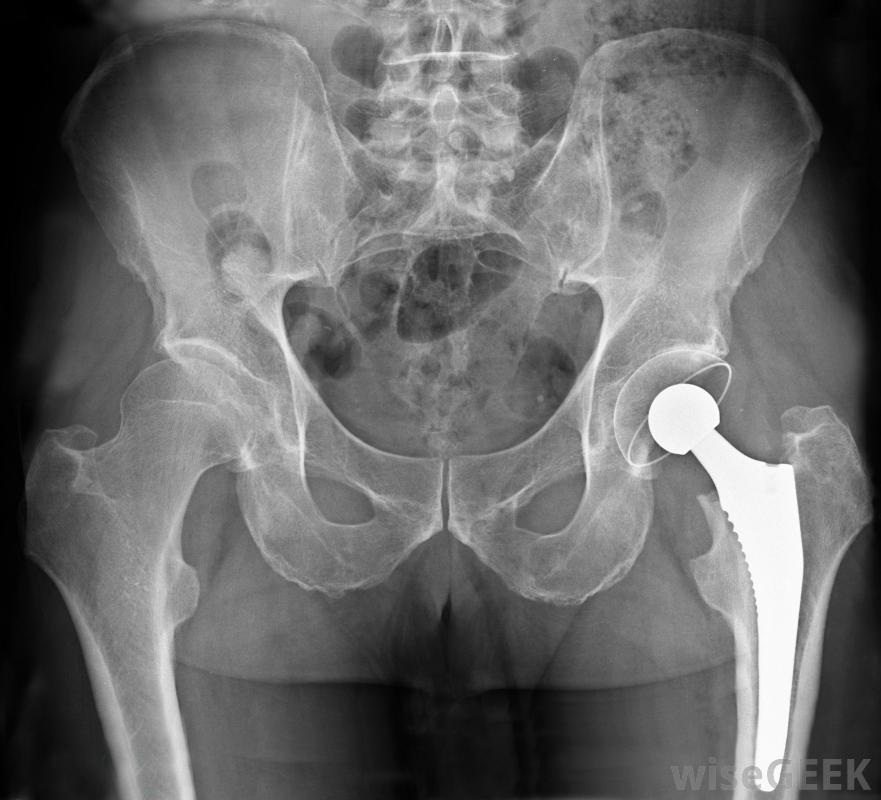

髖部應力性骨折是一種沿著髖部的疼痛性骨折,可能導致無法活動,也無法進行日常活動。患有骨質疏松癥等骨骼疾病的人患此類骨折的風險更高。幸運的是,有一些方法可以治療髖部應力性骨折,并將疼痛降至最低為康復鋪平道路。老年人可能特別容易發生髖部應力性骨折解決髖部應力性骨折的第一步是讓患者盡可能舒服。為此,醫生可能會開一些止痛藥。醫生會確保開的藥不會與你正在服用的其他藥物發生任何不良反應。具體取決于根據您的疼痛程度,您的醫生也可能建議您使用非處方藥,例如基本的抗炎藥。嚴重的髖關節壓力骨折可能需要髖關節置換手術來修復。除了處理髖部應力性骨折帶來的疼痛外,你的醫生也可能要求你戴上某種保護性繃帶,幫助固定臀部這是為了減輕髖部骨折的部分壓力,使你身體的自然愈合過程更容易開始修復損傷。除了包裹髖關節外,你的醫生也很有可能建議在髖部愈合時使用拐杖或助行器治療髖部應力性骨折可能需要物理治療。根據髖部應力性骨折的嚴重程度,可能需要手術來促進愈合過程。如果應力性骨折是某種物理創傷(如意外事故)的結果,尤其如此。手術可以讓醫護人員直觀地評估損傷情況,幫助恢復碎片的排列,如果損傷特別嚴重,可能需要進行髖關節置換手術。這取決于髖關節應力的嚴重程度骨折,可能需要手術來促進愈合。在很多情況下,輕度到中度骨折可以在幾周內愈合,尤其是身體狀況良好的人。然而,當某些類型的衰弱狀況也存在時,如關節炎或骨質疏松癥,恢復時間可能會更長通過采取措施將髖部骨折的壓力降到最低,服用藥物控制疼痛,并在必要時使用支撐設備四處走動,髖部應力性骨折最終會得到修復,你可以回到日常生活中,而不必擔心病情惡化如果髖關節也有關節炎的跡象,則髖關節應力性骨折的恢復時間可能會延長幫助治療髖部應力性骨折。